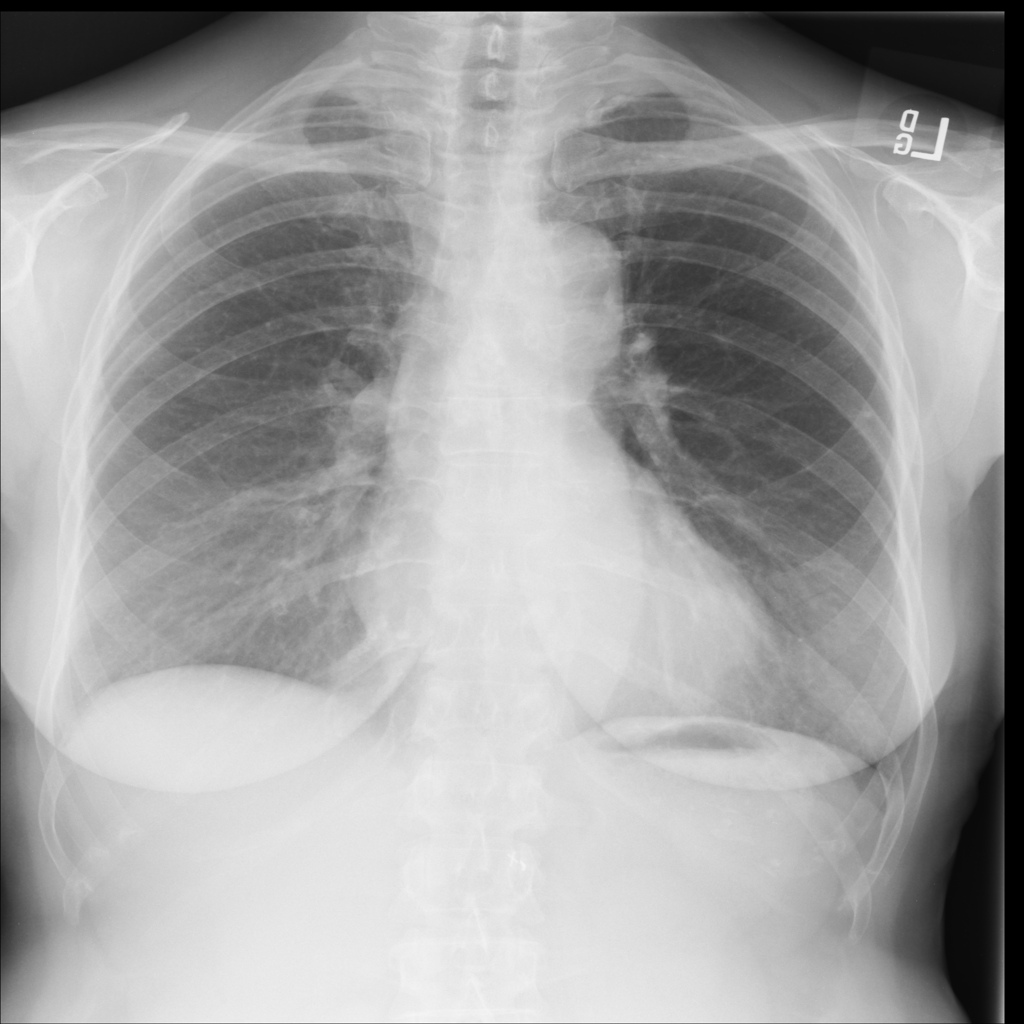

Nodule

A nodule is a small rounded opacity in the lung or chest field. It is a descriptive imaging finding that can be benign or more concerning depending on size, appearance, and context.

Showing up to 90 reference images for Nodule.

PAT-FB8F · IMG-000Nodule

PAT-FB8F · IMG-000

PA